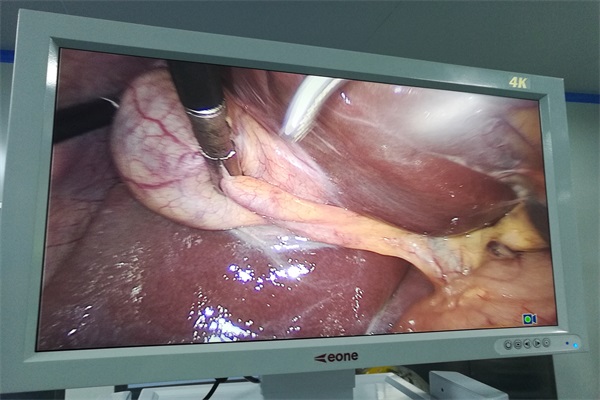

殘留物的沖刷水洗:內(nèi)鏡及器械手術(shù)完畢后立即卸開可卸部分,清洗槽內(nèi)用流動(dòng)水徹底清洗,除去血液、黏液等殘留物質(zhì)并擦干;曲卡及各類手術(shù)鉗、剪類器械、關(guān)節(jié)脫卸用軟毛刷子刷洗,高壓水槍沖洗各腔道、導(dǎo)管、管腔等。